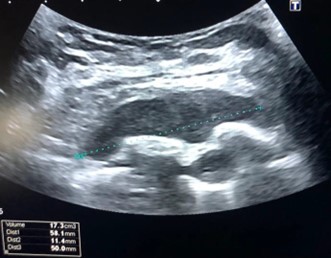

Paciente femenina de 26 años de edad, sin antecedentes patológicos de relevancia, sin dosis de vacuna BCG. Cursa con cuadro clínico de ocho meses de evolución, caracterizado por dolor en región pectoral izquierda intermitente, que se exacerba a la inspiración profunda. En el último mes se palpa masa indurada dolorosa a la palpación a nivel del cuadrante inferior interno de mama izquierda, motivo por el cual se realiza ecografía de partes blandas, donde se observa a nivel retropectoral en íntimo contacto con la parrilla costal imagen hipoecogénica de bordes delimitados, avascular al Doppler color por lo cual se solicita TC de tórax con EV. En ella se observa en topografía del cuarto espacio intercostal, imagen hipodensa con realce periférico tras la administración del contraste que desplaza por efecto de masa el parénquima pulmonar adyacente y se proyecta a la pared torácica anterolateral izquierda; mide 40 mm x 55 mm. Además, se visualiza otra imagen de similares características de base pleural en contacto con el octavo arco costal posterior izquierdo que mide 6 mm x 11 mm.

La ecografía pleural es útil para evaluar la cantidad de líquido y guiar procedimientos como la toracocentesis.